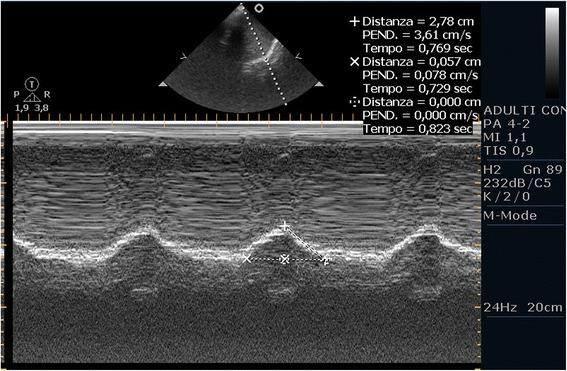

Point-of-care ultrasound of the diaphragm in a liver transplant patient with acute respiratory failure.

In some intensive care, nowadays, ultrasound diagnostics have become an extension of the physical examination (like a stethoscope). In this report, we discuss the case of an acute respiratory failure which arose immediately after the end of general anesthesia. An initial bedside ultrasound evaluation applying the 'BLUE protocol' showed no pathological changes capable of explaining the clinical picture; however, by evaluating also the right and left hemidiaphragms, we made a diagnosis of diaphragmatic dysfunction, which would probably have been difficult to diagnose without the aid of the diaphragm ultrasound. We therefore decided to avoid intubation, transfer the patient to the intensive care unit, and treat him conservatively with non-invasive ventilation only. To our knowledge, this is the first case report that has shown the usefulness of ultrasonography in detecting diaphragmatic dysfunction as a cause of acute respiratory failure with a subsequent change in patient management. The use of bedside ultrasonography provides practical functional information on the diaphragmatic function in patients with acute respiratory failure and can also be easily repeated if follow-up is required. This feature is still held in little consideration, but it can affect the diagnosis and the treatment of critically ill patients.